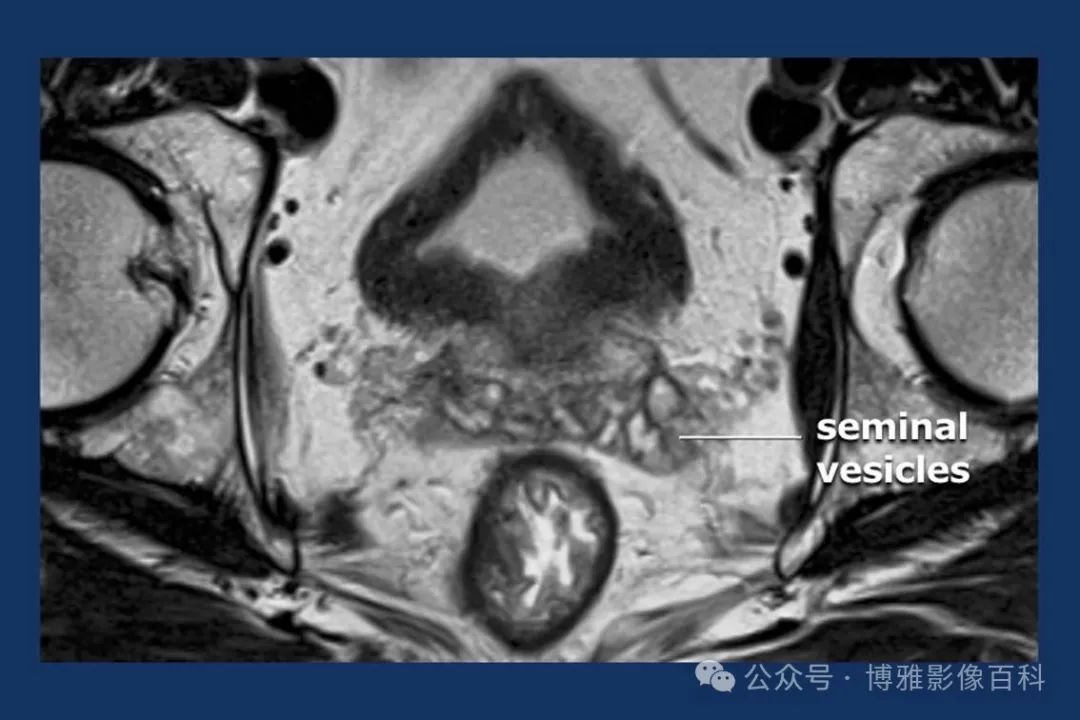

MR 解剖学

前列腺良性增生患者的轴向T2 图像,其他方面正常。外周带是一薄层均匀的高信号,边界清晰连续性的低信号包膜。移行带通常表现为不均匀中等信号,病灶被边界清楚的BPH良性前列腺增生结节所取代。精囊具有均匀T2高信号。未见淋巴结肿大。